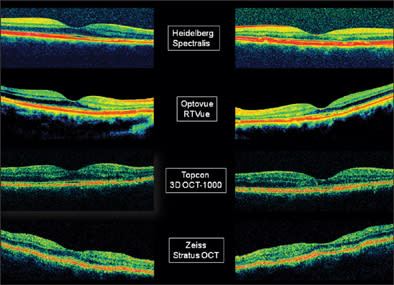

Figure 3. Comparison of images obtained with 3 different spectral-domain OCTs (Heidelberg Spectralis, Optovue RTVue, Topcon 3D OCT-1000) and with 1 time-domain OCT (Zeiss Stratus) of both eyes of the same patient with a history of central serous chorioretinopathy in both eyes.

Figure 4. The same set of images as shown in Figure 3 in pseudo color.